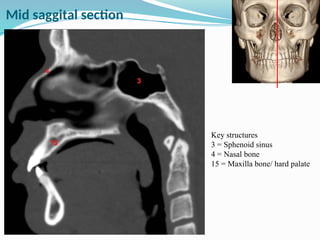

Key structures

3 = Sphenoid sinus

4 = Nasal bone

15 = Maxilla bone/ hard palate

Mid saggital section

Key structures 3 =Sphenoid sinus 4 = Nasal bone 15 = Maxilla bone/ hard palate Mid saggital section